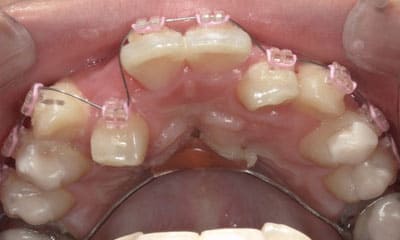

● 先天性の萌出方向異常を部分矯正で治療

藤沢デンタルオフィスの虫歯や破折で先天性の萌出方向異常を部分矯正で治療

01

02

03

04

05

06